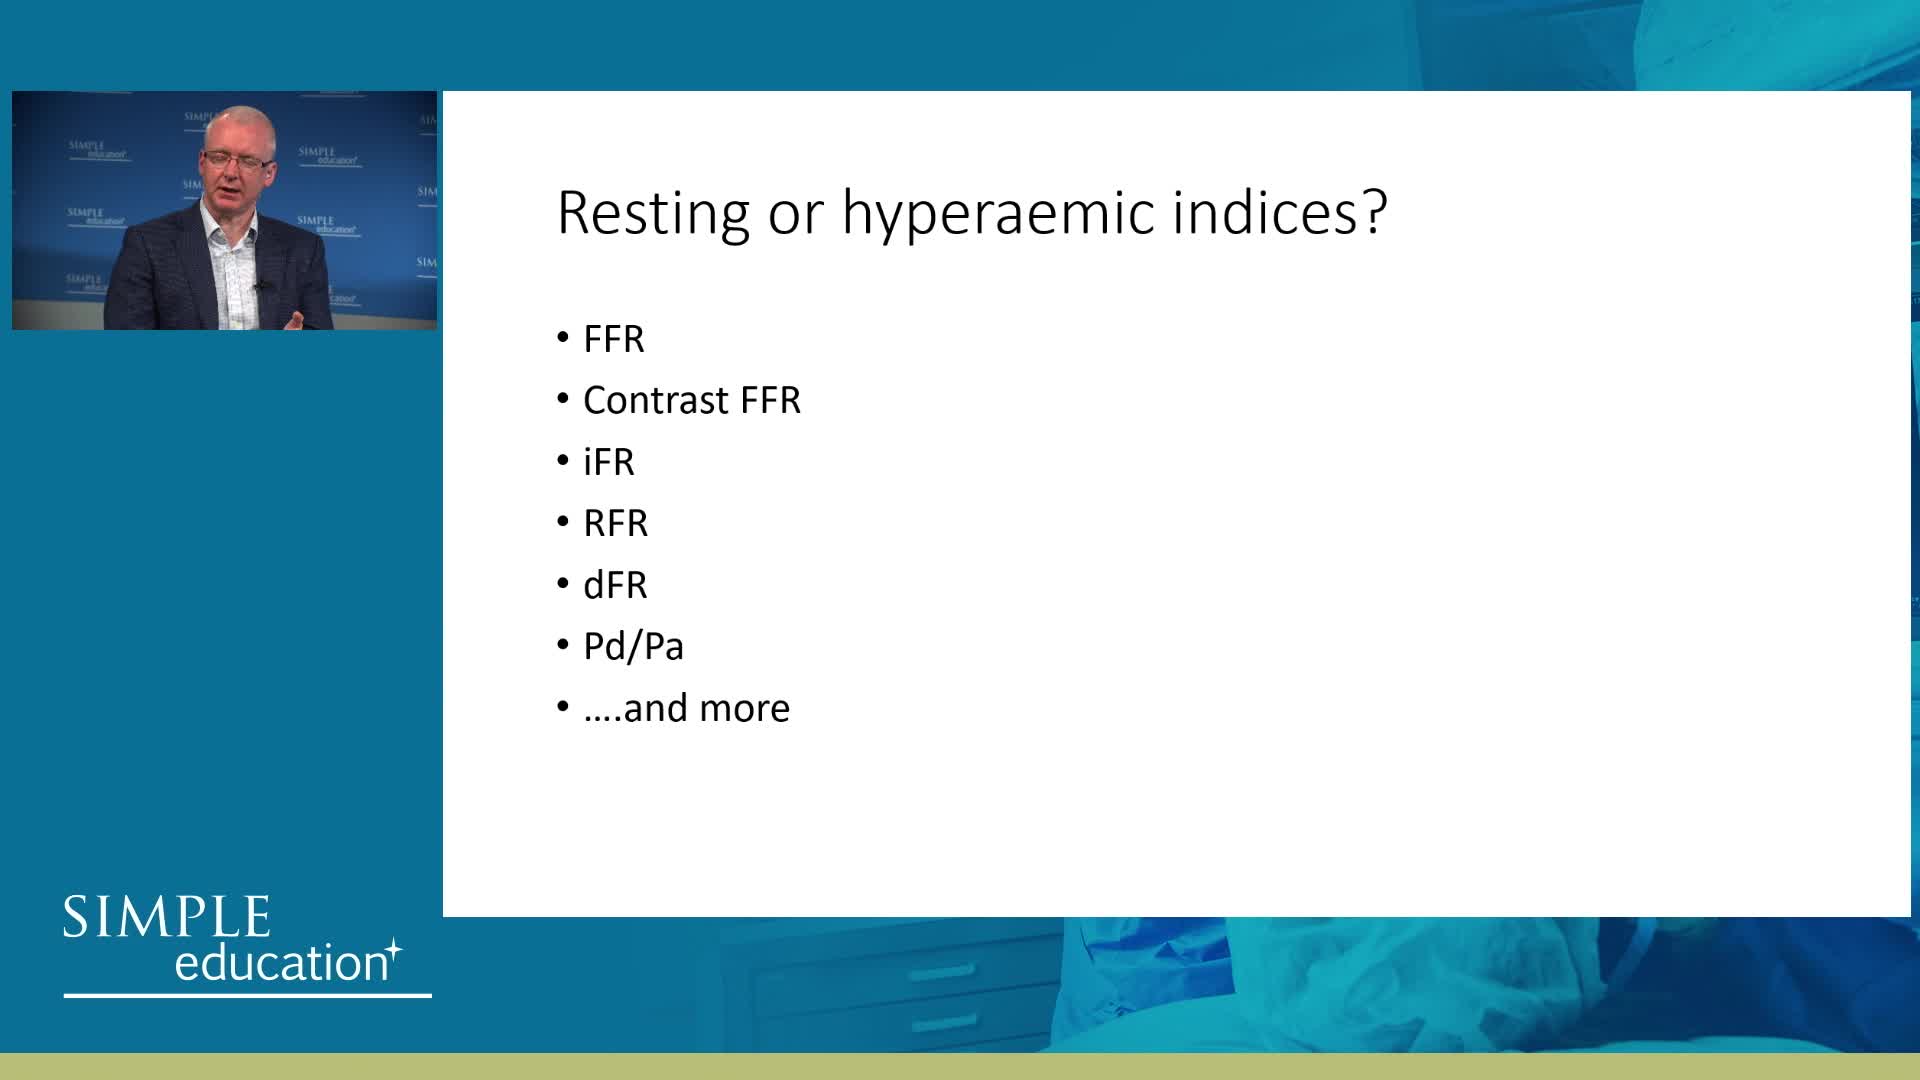

Welcome & Applied coronary physiology to plan and guide PCI-2023 EAPCI Consensus

iFR or FFR in the LAD. What does the clinical outcome data tell us? - Dr Sayan Sen

Breakout session: Common pitfalls of FFR and iFR assessment - Dr Ricardo Petraco

How to perform iFR and FFR, and best-practice measurement tips and tricks - Dr Ricardo Petraco

ABC for using Coronary Physiology in Aortic Stenosis, Primary Percutaneous Coronary Intervention (PPCI)/ACS, Muscle Bridges and Atrial Fibrillation - Dr Ricardo Petraco